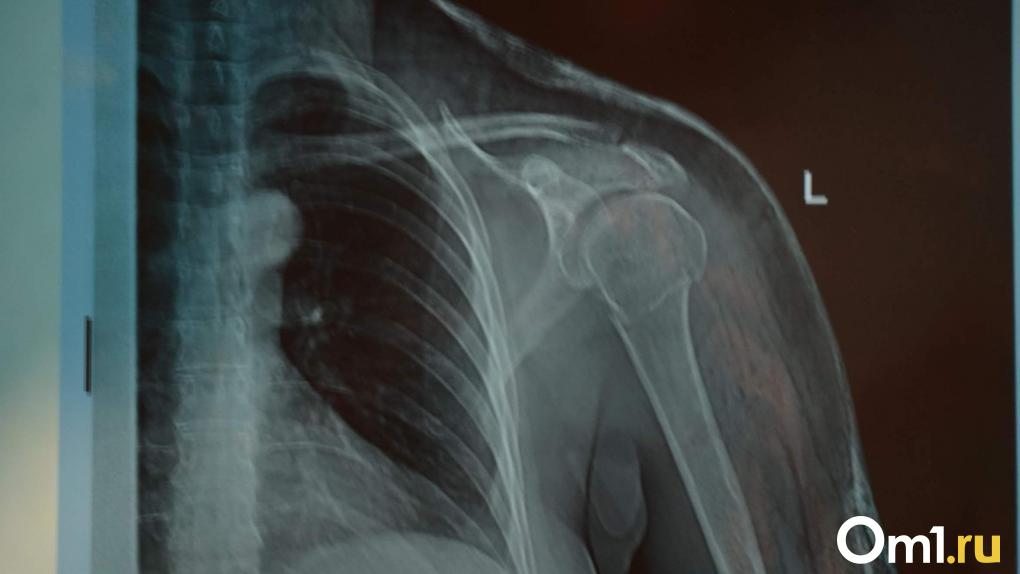

Часто ли можно делать рентген? Разбираем популярные мифы

Подобные процедуры нельзя делать чаще, чем раз в  год

На  самом деле, современные рентгенологические аппараты относятся к  низкодозовым и  не  опасны. При  этом зачастую для  правильного и  своевременного определения проблемы необходимо сделать несколько снимков.

«Для  конкретизации патологии доктор может назначить более развернутые исследования в  виде КТ органов грудной клетки, бронхографии, диаскинтеста. Кому-то  назначают раз в  год, другому  — два. Исследования могут проводить и  чаще, это связано с  клинической картиной. Однако без  надобности этого делать не  стоит, обязательно консультируйтесь с  врачом» ,  — объясняет Виталий Семёнов.

Рентген противопоказан беременным и  кормящим

Это отчасти верно: при  беременности до  16 недель рентген нежелателен. Если возникла острая необходимость, плод защищают свинцовыми фартуками. А  вот кормящим матерям исследования опасаться не  стоит.

«В  этом нет необходимости из-за  низкой дозовой нагрузки на  организм» ,  — говорит рентгенолог.

Рентген зубов  — один из  самых опасных

Этот миф также утратил актуальность: несмотря на  то, что  в  данном случае излучение направлено на  голову, высокая точность современных аппаратов позволяет сконцентрировать его на  нужном месте, например  — конкретном зубе.